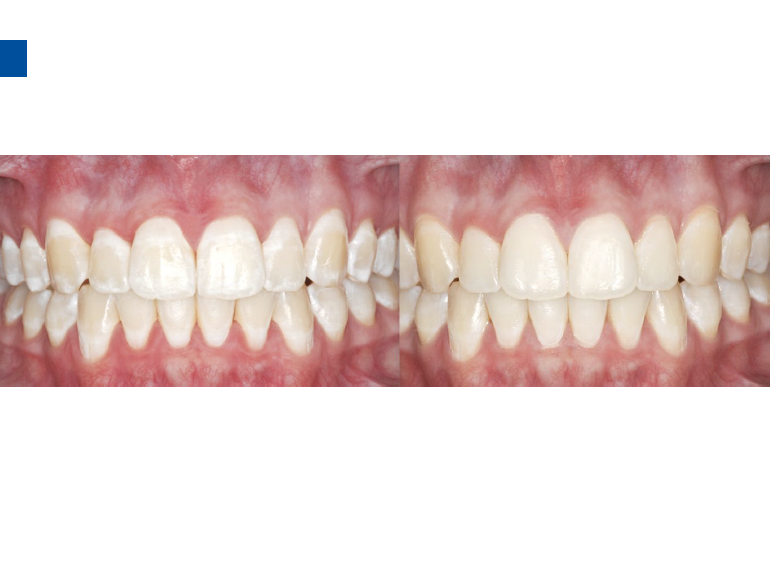

微创牙科治疗是一种全新的龋病治疗理念,着眼于疾病的早发现、早诊断、早治疗。树脂渗透治疗是介于再矿化治疗和充填治疗之间的一种创新的治疗手段,通过微量的去除牙体组织,达到加固脱矿釉质、阻止进一步脱矿的目的。

lcon渗透基于封闭釉质龋空隙的一种特殊树脂的渗透,封闭釉质龋小孔,从而阻断致龋酸传播途径,阻止龋病进一步发展。这种材料操作方法简单,对牙体组织损伤轻微,不用通过麻醉和磨切牙体来达到加固脱矿釉质,同时可以改变釉质龋表面的白色或棕色改变,达到美观修复效果,是对龋病微创治疗的突破。